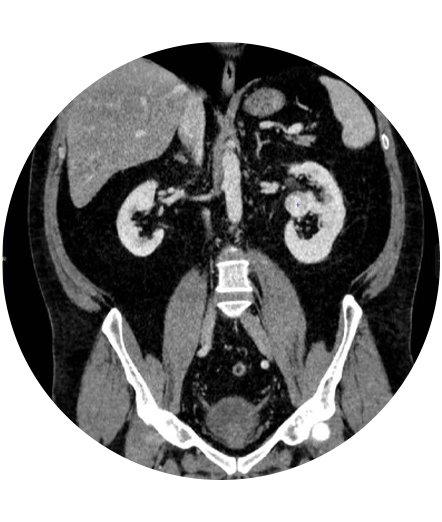

Practicăm urologia modernă care folosește tehnici și proceduri medicale avansate pentru diagnosticarea și tratamentul afecțiunilor urologice, proceduri care sunt actualizate continuu.

Urologia modernă se bazează pe tehnici avansate și inovatoare pentru a oferi tratamente eficiente și personalizate.